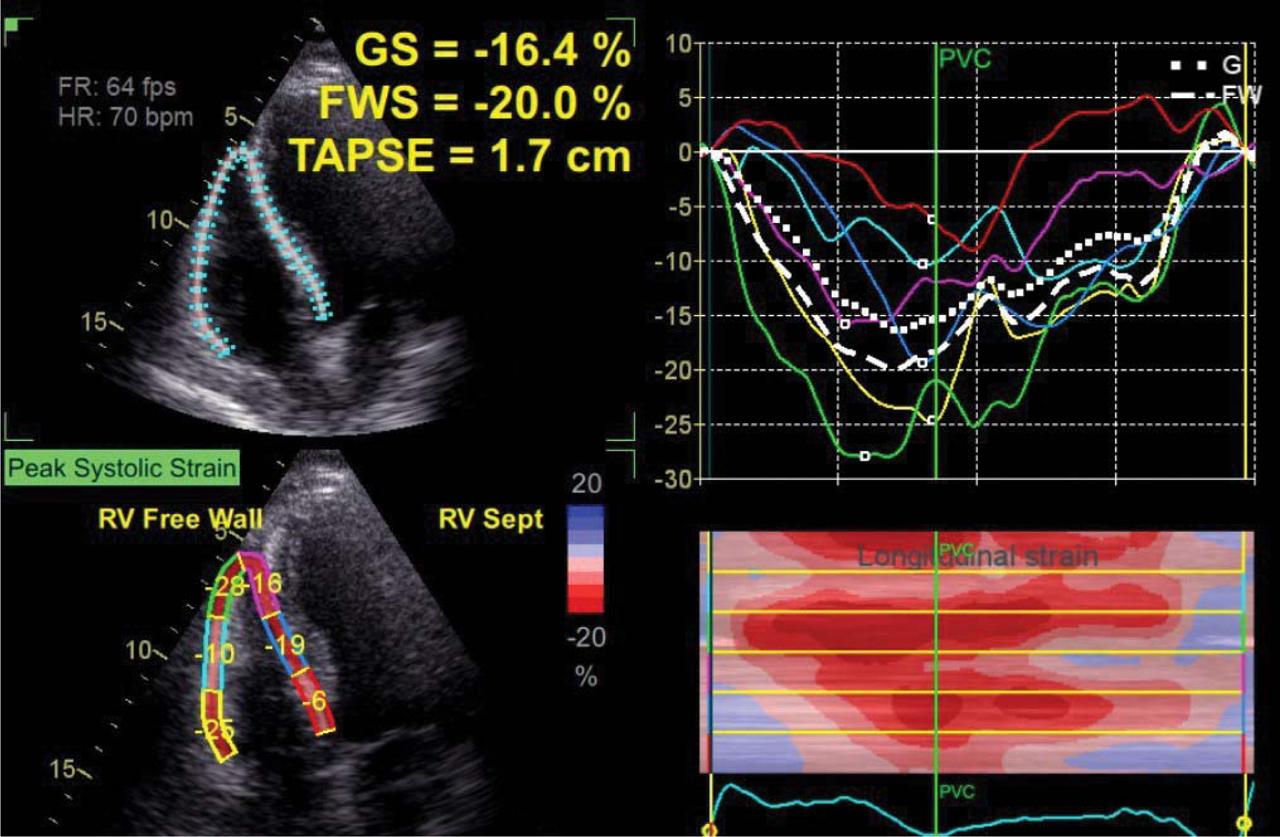

Figure 2